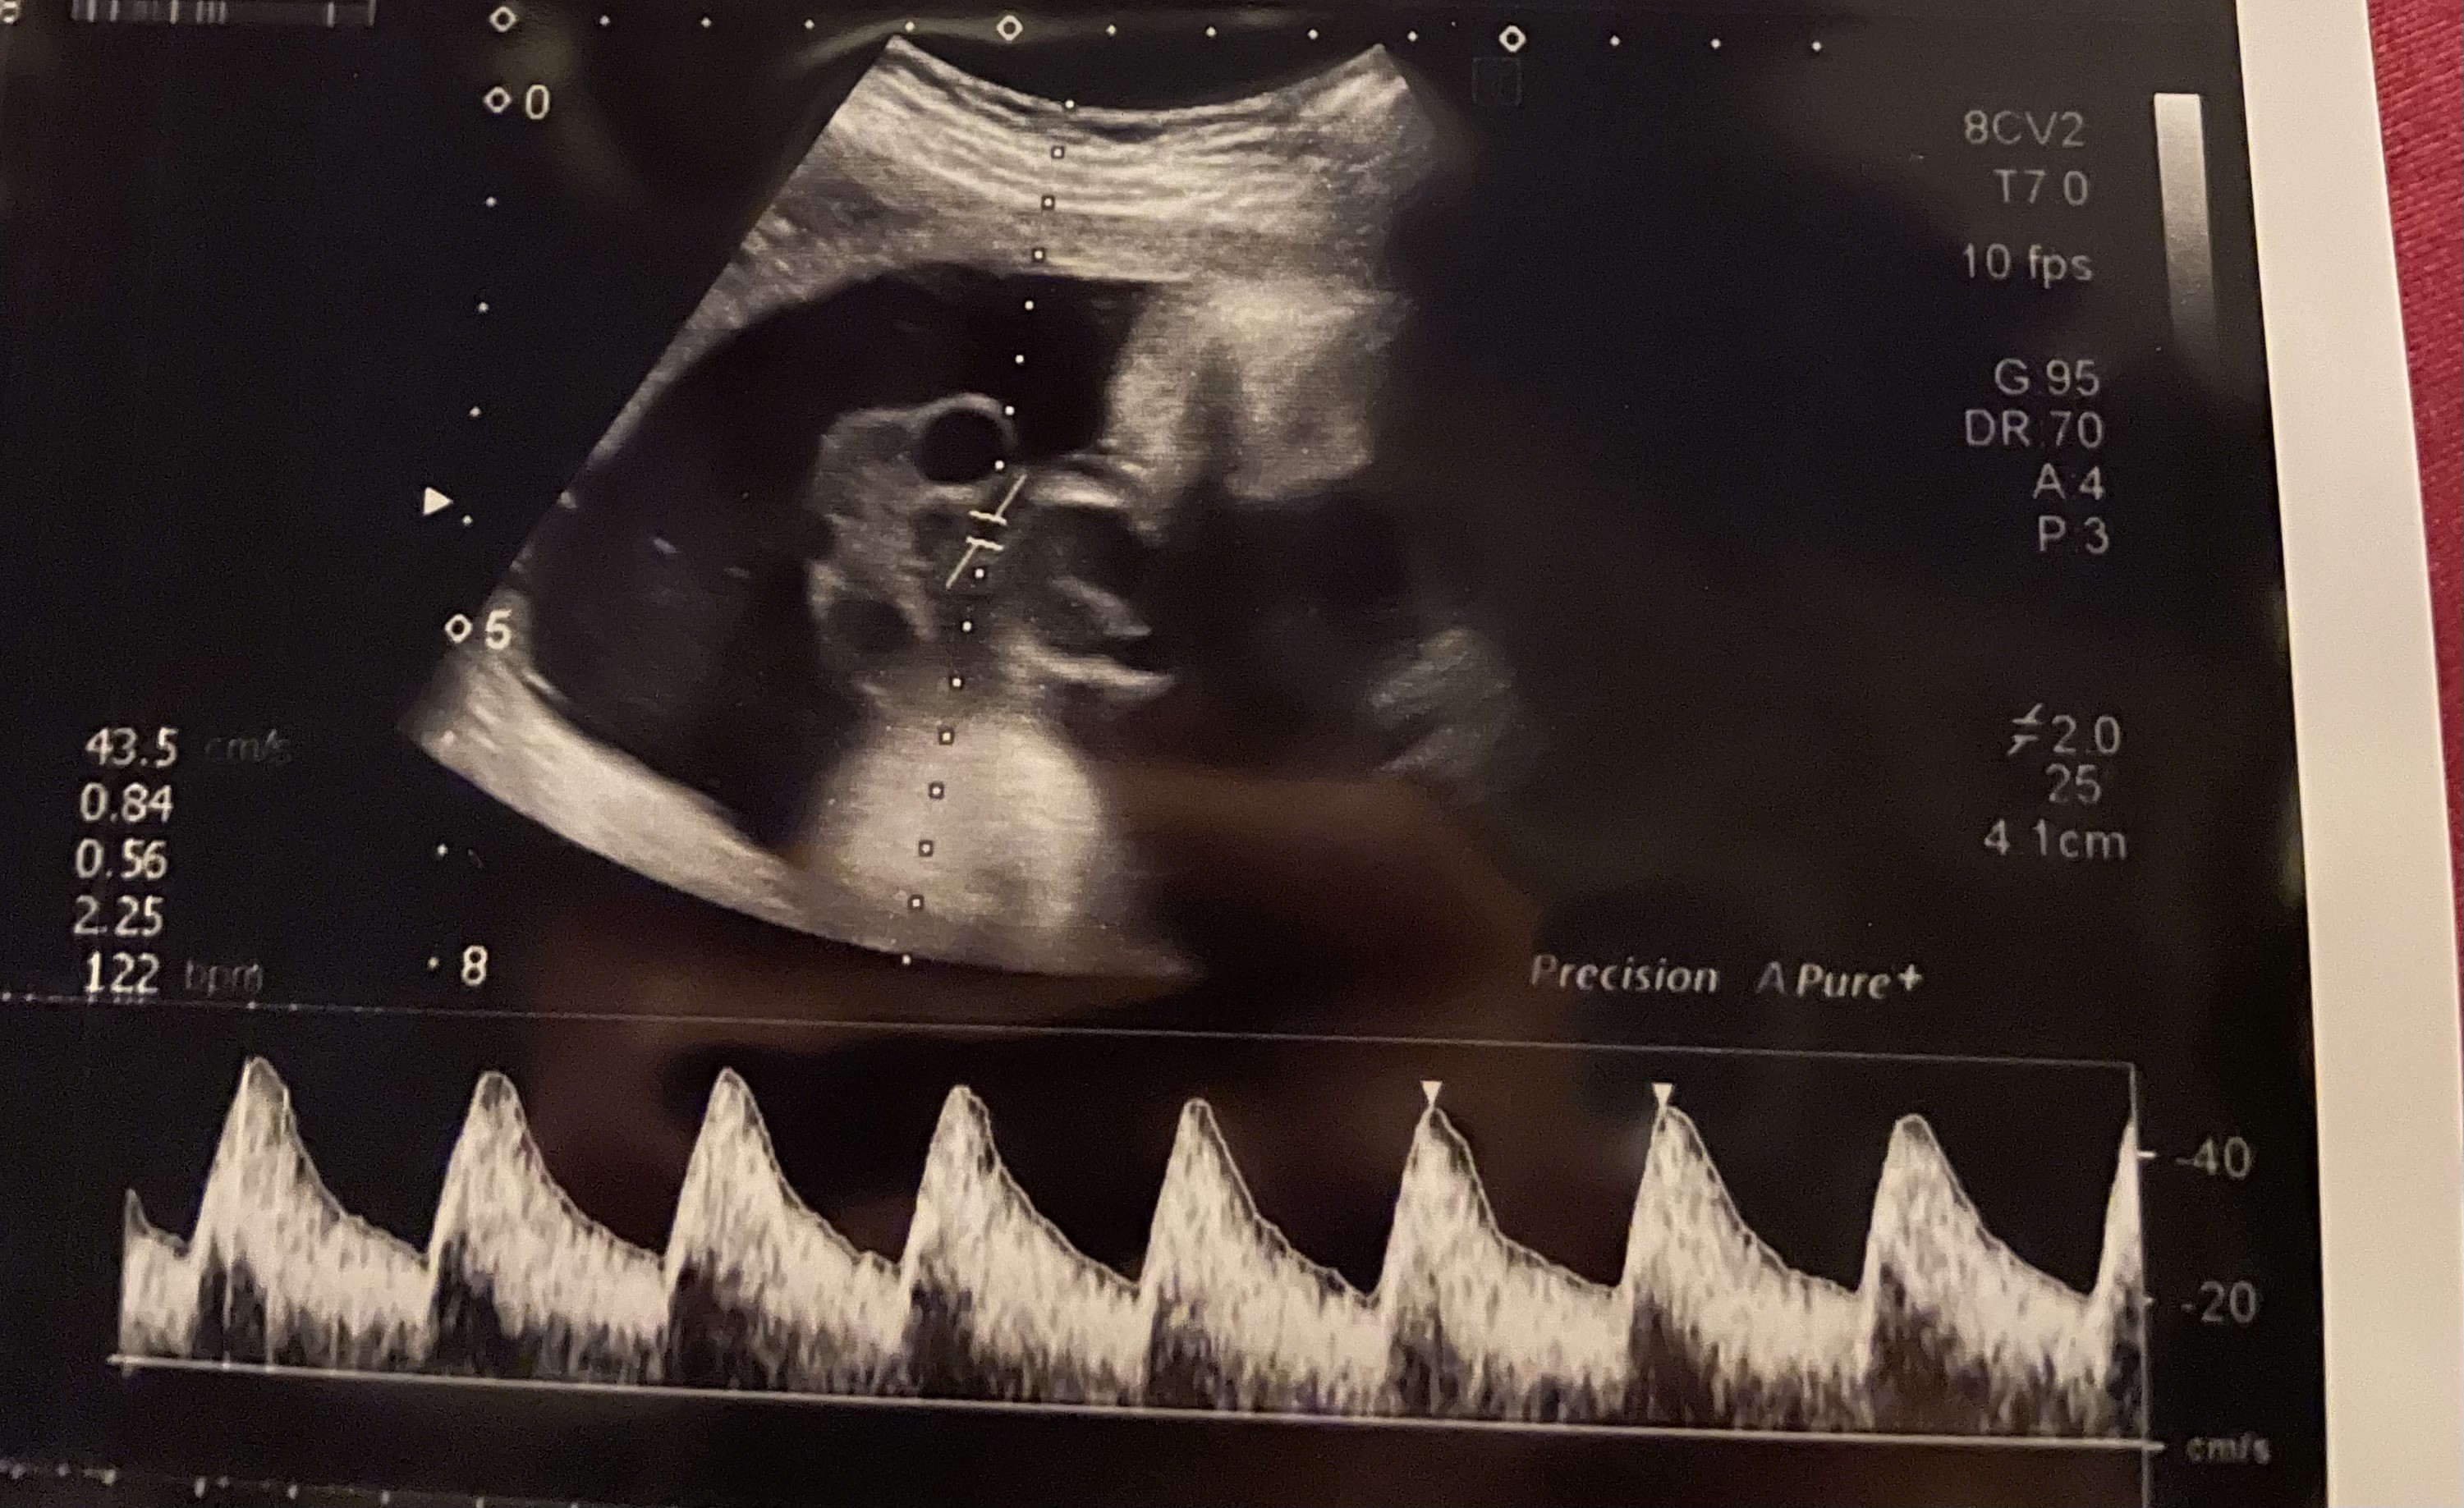

Jak patrzę na Google zdjęcia jak wygląda to badanie przepływów to widzę, ze miałam je robione na wizytach kontrolnych 🤔 Nie wiedziałam, ze to doppler jest.

A sprawdz na wydrukach usg czy nie masz właśnie zrobionych zdjęć przepływów 🤔 spójrz na moje

• 6107E083-5C3D-487F-9699-7C659F1CFD34.jpeg

6107E083-5C3D-487F-9699-7C659F1CFD34.jpeg

1,2 MB · Wyświetleń: 101